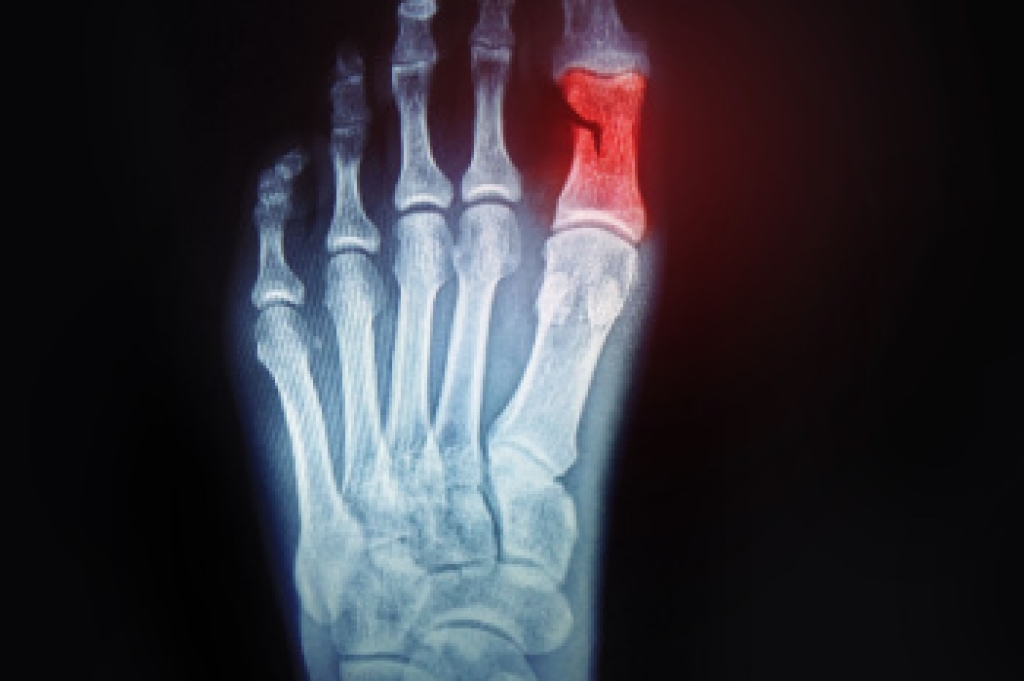

A broken toe occurs when one of the bones in the toe is fractured due to excessive force or impact. This type of injury is common and can range from a small crack to a complete break. The most frequent cause of a broken toe is trauma, such as stubbing the toe against a hard object or dropping something heavy on it. Athletes and active individuals are more prone to this injury due to the physical demands of sports and activities that involve running or jumping. Other causes include accidents, falls, or even repetitive stress over time. Symptoms of a broken toe include severe pain, swelling, bruising, and difficulty moving the toe. In some cases, the toe may appear misaligned or deformed. Proper diagnosis through an X-ray is important to determine the severity of the fracture and ensure appropriate treatment. If you have broken your toe, it is suggested that you visit a podiatrist as quickly as possible who can begin the correct treatment for proper healing.

A broken toe occurs when one or more of the toe bones of the foot are broken after an injury. Injuries such as stubbing your toe or dropping a heavy object on it may cause a toe fracture.